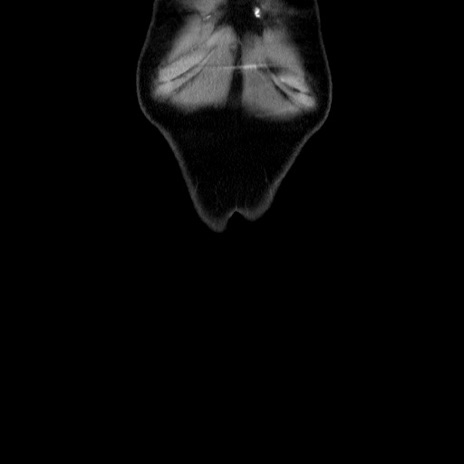

矢状断像

【症例】60歳代 男性

【主訴】右鼠径部膨隆

【現病歴】1年程前より右鼠径部膨隆あり。自己にて還納可能だったため放置していた。3時間前より右鼠径部の脱出を認め、還納困難となり受診。

【身体所見】右鼠径部に小児頭大の膨隆あり。弾性硬であり、用手還納は困難。左鼠径部にも膨隆を認める。脱出はなし。